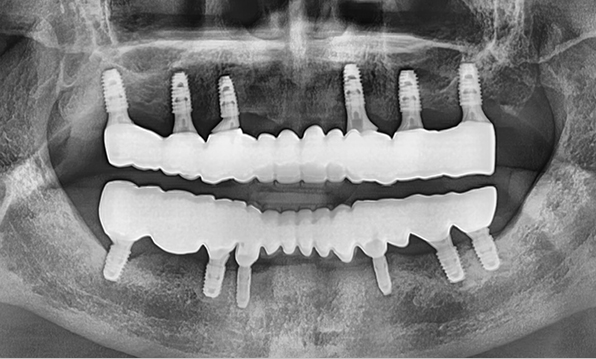

전체 임플란트

위 아래 치아가 정확하게 맞아야하는 고난이도 임플란트

임상 경험이 많은 숙련된 전문의의 섬세한 기술력이 중요합니다.

정확성 높은 식립의 노하우

3D 디지털 진단을 통한 체계적인 계획

전체 임플란트는 위턱과 아래턱의 교합, 잇몸뼈의 상태 및

얼굴 변화 등 모든 것을 고려해 식립해야 합니다.

서울더자연치과는 3D 디지털 기술의 정밀 진단을 바탕으로

수술 계획을 세워 수술을 집도합니다.